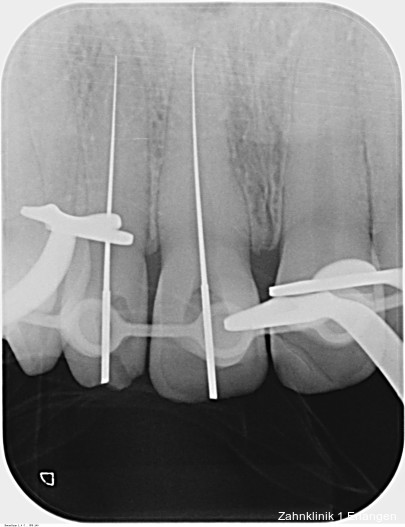

Zu den wesentlichen diagnostischen Verfahren, die zur Erfassung des Pulpastatus herangezogen werden, gehören neben der Inspektion und der röntgenologischen Bildgebung die Sensibilitätsprüfung sowie der Perkussionstest. Der Inspektion kommt insbesondere bei der Erstbehandlung eine wesentliche Rolle zu. Hierbei wird abgeklärt, ob es sich bei Zahnfrakturen um eine schmelzbegrenzte Verletzung handelt, ob das Dentin mitbetroffen und ob zusätzlich die Pulpa exponiert ist. Bei Dislokationsverletzungen wird das Ausmaß der Positionsveränderung erfasst und ob zusätzliche Gewebe wie Knochenstrukturen oder umliegende Weichgewebe betroffen sind. Auch können Farbveränderungen des Zahnes erfasst werden. Die Röntgendiagnostik zum Zeitpunkt des Unfalles gibt Aufschluss über die Größe des Pulpenkavums und das Lumen des Wurzelkanals, den Stand des Wurzelwachstums und die periapikalen Verhältnisse. Des Weiteren finden sich möglicherweise Hinweise auf eine Wurzelfraktur.

Bei ausgeprägten Dislokationsverletzungen stellt die Schädigung des Parodonts die dominierende Verletzung dar, die auch zu Spätfolgen und Komplikationen führen kann. Verletzungen des Endodonts sind im Hinblick auf den Zahnerhalt vergleichsweise unbedeutender, da die Wurzelkanalbehandlung eine Infektion relativ sicher verhindern oder beseitigen kann. Die Erstversorgung schließt im Wesentlichen die Repositionierung und Schienung zur Ruhigstellung der betroffenen Zähne ein.3 Spätestens ab einer Positionsveränderung von 2 mm ist bei Zähnen mit abgeschlossenem Wurzelwachstum sicher von einem irreparablen Schaden der Pulpa auszugehen.2 Wichtig ist es, zeitnah, in der Regel während der Schienungsdauer, die Wurzelkanalbehandlung einzuleiten, um eine bakterielle Besiedelung des Wurzelkanals zu verhindern. Dabei reicht es zunächst aus, den Zahn zu eröffnen, desinfizierend zu spülen und eine medikamentöse Einlage einzubringen. Wird dies unterlassen, entwickeln sich bei entsprechender parodontaler Schädigung infektionsbedingte Resorptionen, die rasch fortschreiten und innerhalb relativ kurzer Zeit bis zum Zahnverlust führen können.

Wesentlich sind die Nachkontrollen, die bei schwerwiegenderen Verletzungen und hohem Komplikationsrisiko engmaschiger erfolgen sollten. Es bietet sich das Schema an, die Nachkontrollzeiträume jeweils zu verdoppeln. Für die meisten Verletzungsarten sollten nach der Akutbehandlung klinische Kontrollen zu den Zeitpunkten nach drei und sechs Wochen sowie nach drei, sechs und zwölf Monaten durchgeführt werden.3